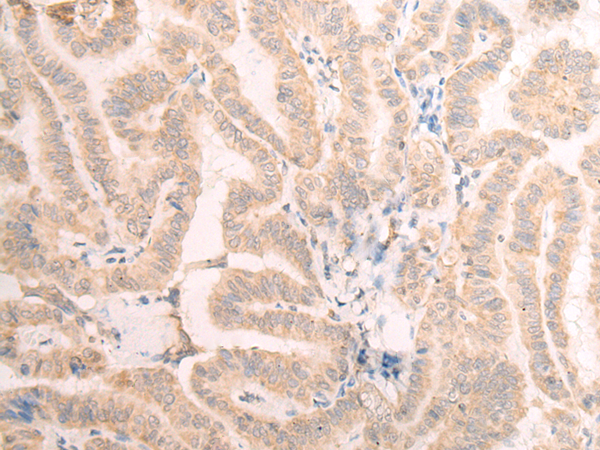

分类: 科研抗体货号: P06438别名: ENT2; DER12; HNP36应用: WB,IHC反应种属: Human